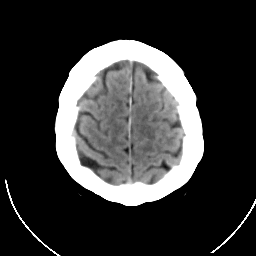

CT Study #1 -- Slice #20